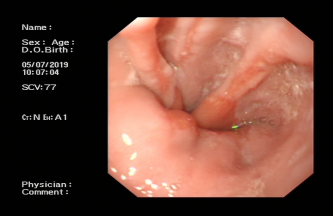

Ⅲ、POEM治疗贲门失弛缓症